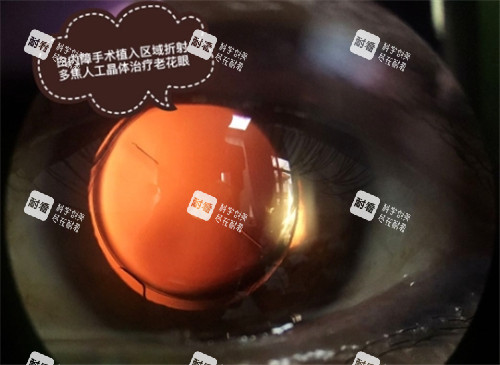

“免费手术是不是只能用较便宜的晶体?”这是许多患者较关心的问题。以北京医院为例,免费手术通常采用超声乳化白内障吸除术,搭配国产单焦点人工晶体,这种组合技术成熟、修养快,能满足基本视力需求。若患者希望选择更高端的多焦点或散光矫正型晶体,需自费补差价。例如,某品牌多焦点晶体市场价约1.2万元,患者需自行承担3000-5000元。

晶体选择:免费≠“低质量”,国产晶体技术成熟

“免费手术用的晶体是不是质量差?”这是许多患者的顾虑。实际上,国产折叠晶体已通过各国药监局认证,技术成熟,术后结果与进口晶体差异不大。例如,某国产单焦点晶体市场价约2000元,已广泛应用于免费手术,患者术后视力修养良好。若追求更高品质,可自费升级至多焦点晶体(市场价1.2万-3万元),但需评估自身经济能力。